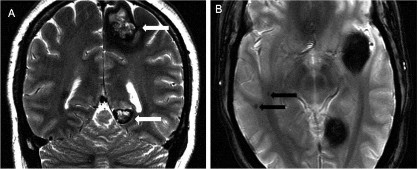

Hình 1.9. Dị dạng u mạch thể hang tính chất gia đình

Nguồn trích dẫn: Hiba AH, Lawrence JH. Uptodate. 2018; Topic 14040 [29].